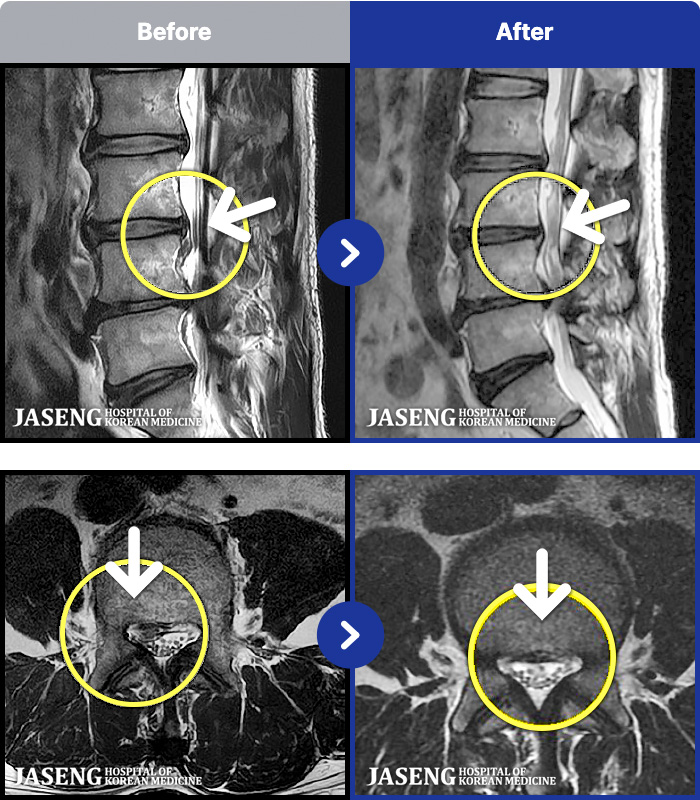

[ϻ] 24.07.25~25.08.01

ȯںп Ǹ ǿ ԿǾ, ο ġ ۿ Ƿ ġḦ Ͻñ ٶϴ.